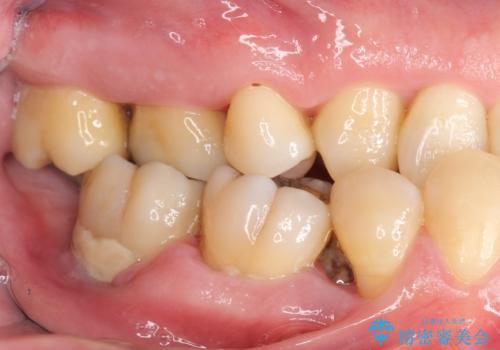

インプラント治療を併用した全顎歯周病治療

全体的に重度の歯周病が認められ、抜歯が必要な部位はインプラント治療を、残すことのできる歯には再生治療を含めた歯周病治療を行い全体的な治療を進めてきます。

工程も多く、治療期間も長くなりがちですが、しっかりと通っていただいたおかげで安定した噛み合わせで食事を楽しむことができるようになりました。